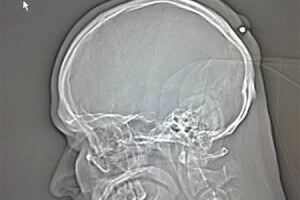

Повреждение черепной коробки

Выживший при огнестрельном попадании в голову, станет калекой на всю оставшуюся жизнь. Он может частично или полностью лишиться возможности к мыслительной деятельности, быть частично или полностью парализованным, лишиться слуха, зрения или других чувств.

Пострадавший может впасть в состояние комы, в котором он проведёт оставшуюся жизнь.

Ранение в голову часто сопровождается:

- Потерей сознания или оцепенением;

- Рвотой;

- Резким изменением пульса;

- Повышенной или пониженной температурой тела;

- Частым дыханием;

- Ушибом и даже омертвением мозга;

- Попаданием в мозг осколков черепных костей.

Смерть человека наступает стремительно.